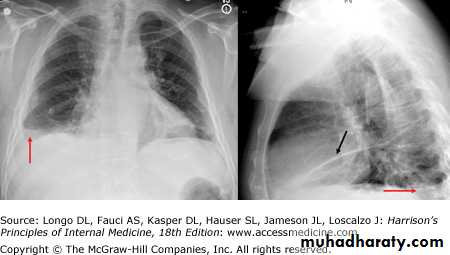

- (CXR) :The classical appearance of pleural fluid on the erect PA chest film is of a curved shadow at the lung base, blunting the costophrenic angle and ascending towards the axilla

Fluid appears to track up the lateral chest wall.

Around 200 mL of fluid is required to be detectable on a PA chest X-ray, but smaller effusions can be identified by ultrasound or CT.

Pleural fluid localised below the lower lobe ('subpulmonary effusion') simulates an elevated hemidiaphragm.

Fluid localised within an oblique fissure may produce a rounded opacity, simulating a tumour.